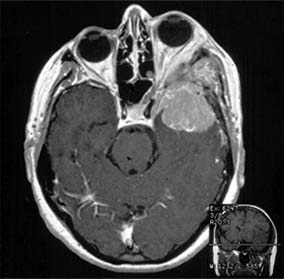

Figure 14-18

Figure 14-18: Axial MRI of sphenoid wing meningioma causing proptosis.